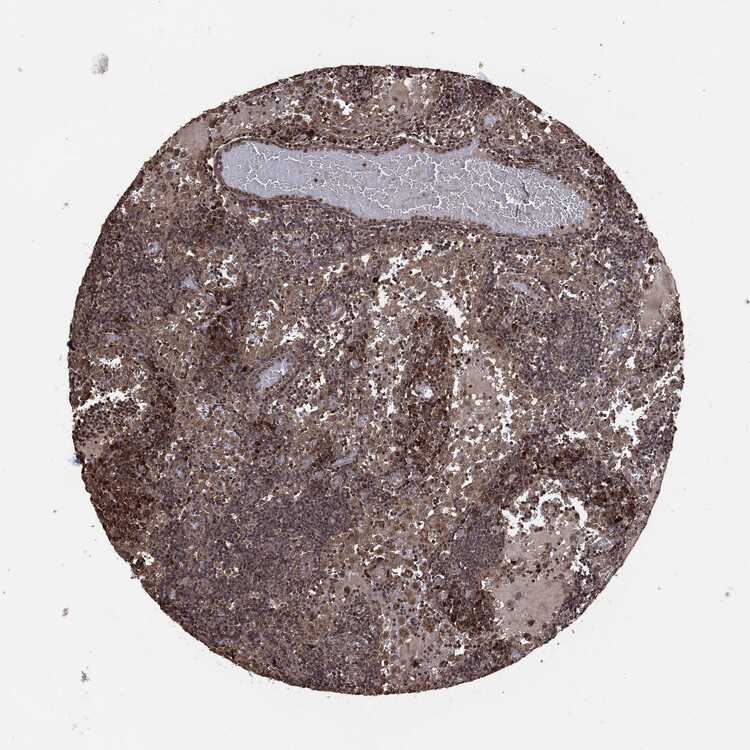

TISSUE PRIMARY DATA LYMPH NODE Show tissue menu

Lymph node

LYMPH NODE - Antibody stainingi

Antibody staining in the annotated cell types in the current human tissue is reported as not detected, low, medium, or high, based on conventional immunohistochemistry profiling in selected tissues. This score is based on the combination of the staining intensity and fraction of stained cells.

Each image is clickable and will lead to virtual microscopy that enables deeper exploration of all samples and also displays staining intensity scores, fraction scores and subcellular localization as well as patient and tissue information for each sample.

Antibody CAB069425Antibody CAB080053Antibody CAB080065Antibody CAB080070Antibody CAB080081Antibody CAB080095Antibody CAB080097

Germinal center cells Not detectedLow-MediumNot detected-Not detected

Non-germinal center cells Not detectedNot detectedMediumLowNot detectedMediumMedium